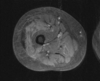

Sign and diagnosis?

Double PCL

- Medial meniscus bucket handle tear

- Proves ACL is intact